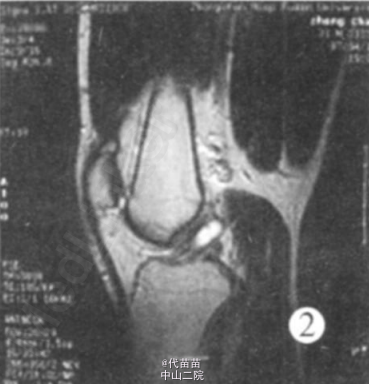

查体: 左膝关节无肿胀, 浮髌实验阴性, 左膝伸0° , 屈 130° 疼痛, McMurray 征阴性, 前后抽屉实验阴性, Lachman实验阴性。 MRI 报告示: (1) 左膝前交叉韧带囊肿。(2) 左膝关节腔内少量积液(图 1、2)。

初步诊断: 左膝前交叉韧带囊肿 手术所见: 患者在全麻下行左膝关节镜下前交叉韧带囊肿切除术。 取左膝髌旁内外侧常规入路, 见膝关节腔内无黏连,滑膜无增生肥厚及充血水肿, 股骨髁及胫骨平台软骨光滑, 内外侧半月板形态大小正常, 表面光滑无撕裂。 前交叉韧带后束中段可见一囊肿, 大小约 2 c m×1 c m×1 c m, 囊肿长轴与前交叉韧带长轴一致。 探针探查囊肿壁韧, 前交叉韧带完整性好,张力略低。 镜下手术切除囊肿, 小心咬除部分囊壁 , 用刨削器清除囊肿, 将切下的囊壁及囊肿碎片送病理。 囊肿切除后发现前交叉韧带松弛, 无张力。 遂决定行前交叉韧带重建, 镜下切断前交叉韧带, 打磨其股骨及胫骨止点。 在胫骨结节内侧 1cm, 关节线下 3 c m处作一纵形切口约 3cm, 切开缝匠肌筋膜,暴露半腱肌和股薄肌止点、分离, 用取腱器取出半腱肌和股薄肌肌腱各 1根, 然后, 四股编织后形成 12 c m长直径 8 mm的植入物备用, 在关节镜下用胫骨导向器调整角度为 45° , 打入导针, 检查导针位置在胫骨平台前 1/3处, 股骨止点在过顶处, 用8mm钻头, 扩胫骨隧道, 然后用股骨导向器再次确定股骨隧道开口, 后用 8 mm的钻头扩股骨隧道, 最后用带针导针将编织好的韧带引出, 股骨部分用强生Rigidfix固定, 胫骨处用强生Intrafix螺钉固定, 用探针检查植入前交叉韧带稳定后, 再次检查各个关节间室后, 无误注射透明质酸钠 5ml 防止黏连后, 关闭伤口, 加压包扎。囊肿病理检查结果: 纤维囊壁组织。诊断: 左膝前交叉韧带囊肿